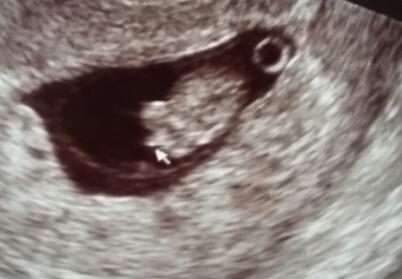

Was denkt ihr 11+4 (junge ???)

Was meint ihr kann es sich noch als Mädchen entwickeln ?

Bild zu Was denkt ihr 11+4 (junge ???) - Schwanger - wer noch? Rund um die Schwangerschaft

Ich finde es zwar früh... eindeutig erkennbar aber auch... falls sich der Penis nicht doch noch im Fruchtwasser auflöst

In dem Alter haben alle Babys Geschlechtsknospen. Männlein und Weiblein sehen nahezu gleich aus und unterscheiden sich nur im Winkel (den sie zum Körper stehen)

Bei meinen 3 Mädels sah es immer gar nicht so aus in der 12-14.ssw, sondern viel dezenter. Also ich würde jedenfalls NICHT auf ein Mädchen tippen...

Hallo,ich würde nicht zwangsläufig von einem Jungen ausgehen. Unser Mädchen sah in der 12.SSW nicht sehr anders aus. LG, Anja

Jaa sieht man aber bei dir ist dünner ausgeprägt als bei meiner Foto, naja wie auch immer dan werde ich eben Mama von zwei Jungs Mehr weiss ich am Montag falls man was sieht Ich fand ein Ultraschalbild auf google das auch so ausieht sogar nochmehr sichtbarer und es kam beim Blutest wie ich lesen konnte ein Mädchen raus...